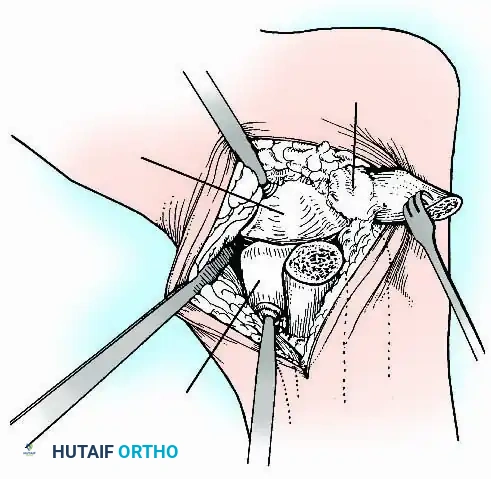

Anterior Approach

The anterior approach is typically performed through the internervous plane between the extensor hallucis longus (EHL) and the extensor digitorum longus (EDL), often utilizing the anterior tibial tendon sheath. This provides excellent, direct visualization of the central tibiotalar articulation and allows for easy posterior translation of the talus. However, access to the medial and lateral gutters is restricted, sometimes necessitating accessory incisions.

Transmalleolar (Transfibular) Approach

This approach utilizes a lateral incision over the distal fibula. A transfibular osteotomy is performed, reflecting the distal fibula distally or excising it entirely to be used as autograft. This provides unparalleled exposure of the lateral half of the joint and the posterior facet. It is highly effective for correcting severe varus/valgus deformities. A supplementary medial incision (medial malleolar osteotomy) can be added for complete joint exposure.

Preparation of Joint Surfaces

- Contour Preservation (Fishscaling): The remaining articular cartilage is meticulously denuded using curettes, and the subchondral bone is "fishscaled" or aggressively petalled with a sharp osteotome. This preserves the native ball-and-socket contour of the ankle, maximizing inherent bony stability and minimizing limb shortening.

- Planar Resection (Parallel Cuts): Two parallel cuts are made—one through the distal tibial plafond and one through the talar dome—using an oscillating saw. This technique resects a minimal amount of bone but creates perfectly flat, highly vascular cancellous surfaces that allow for excellent apposition and easy posterior translation of the talus. Extramedullary alignment guides (often repurposed from total knee arthroplasty systems) can be utilized to ensure precise, parallel resections.